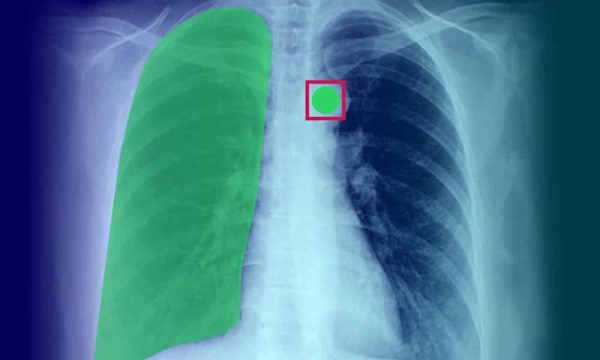

Представьте себе врача, который пытается разглядеть небольшое новообразование на зашумленном рентгеновском снимке. Каждая минута, потраченная на анализ, может быть критически важна для пациента. Эффективные системы анализа медицинских изображений, способные уменьшать шумы и улучшать видимость важных деталей, могут существенно повысить точность и скорость диагностики, что в конечном итоге спасет жизни.

Мы успешно применяли CNN для уменьшения шумов на рентгеновских снимках легких и МРТ головного мозга. В обоих случаях мы получили значительное улучшение качества изображений, что позволило врачам более точно диагностировать заболевания.

При разработке системы для рентгеновских снимков мы использовали архитектуру U-Net, которая хорошо подходит для задач сегментации и восстановления изображений. Мы обучили сеть на большом наборе данных, состоящем из пар зашумленных и чистых рентгеновских снимков. В результате мы получили систему, способную эффективно подавлять шум, сохраняя при этом важные анатомические структуры.